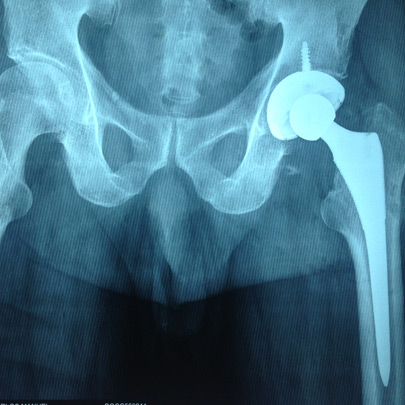

Fracturas y luxaciones

Prótesis